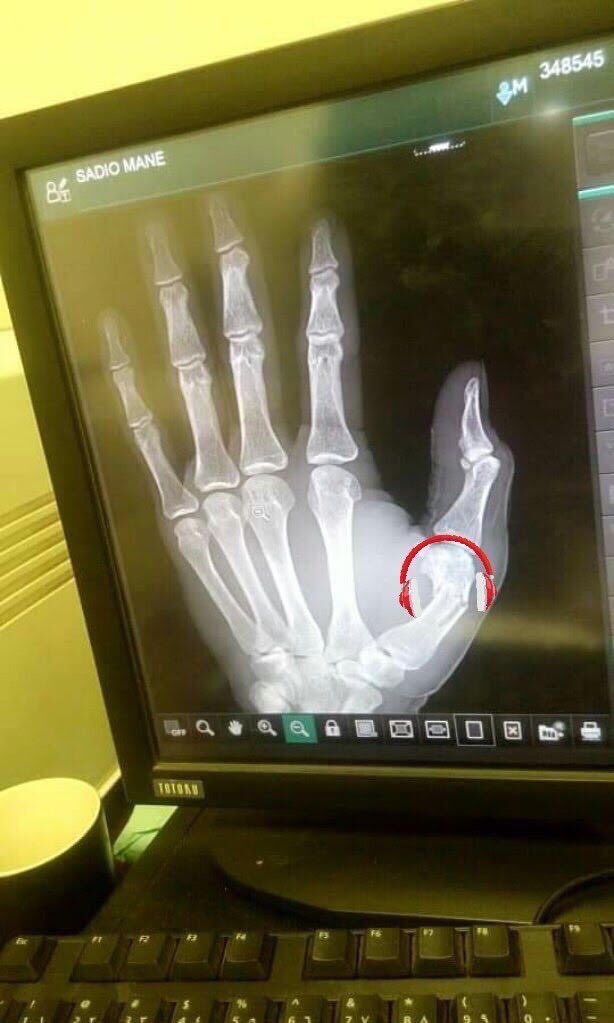

Un autre coup dur pour la Tanière! Après Idrissa Gana Gueye, voila Sadio Mané forfait pour le match de demain contre le Soudan. Blessé à la main gauche lors du match aller au stade LSS (3-0), l'attaquant sénégalais ne pourra pas disputer la rencontre de la quatrième journée des éliminatoires de la CAN 2019, estime le docteur Abdourahmane Fedior. « Sadio s’est blessé à la main gauche lors du match aller. On lui a fait une radio, ce n’est pas si grave mais il est forfait pour le match de demain. Il va surement rentrer en club ce mardi », annonce le médecin de l’équipe nationale.